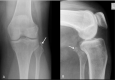

Distal biceps femoris tendon is an unusual site of calcific tendinitis and a rare cause of knee pain. We present a case of 72-year-old lady who presented with a six-month history of pain over the lateral aspect of knee. Subsequent imaging demonstrated calcific deposits within the biceps femoris tendon substance. She was then successfully treated with ultrasound-guided barbotage of the calcium deposits and peri-tendinous corticosteroid injection. Clinical awareness of the unusual sites of calcific tendinitis with imaging evidence is important for early diagnosis and appropriate management.